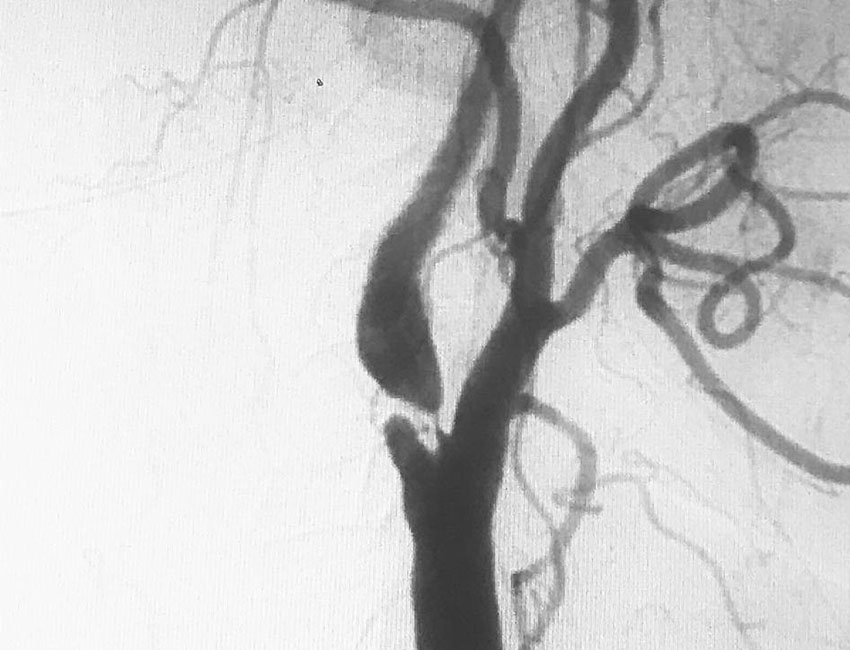

Η καρωτιδική νόσος είναι μια πάθηση που επηρεάζει τις καρωτίδες αρτηρίες, οι οποίες είναι υπεύθυνες για την αιμάτωση του εγκεφάλου. Αυτή η νόσος προκαλείται κυρίως από την δημιουργία αθηρωματικής πλάκας ή αρτηριοσκλήρυνση (πάχυνση του τοιχώματος) στην κοινή και έσω καρωτίδα.

Η διάγνωση της καρωτιδικής νόσου γίνεται μέσω έγχρωμης υπερηχογραφίας (triplex) των καρωτίδων. Ακολουθεί CTA ( αξονική αγγειογραφία ) αγγείων τραχήλου – εγκεφάλου για προσδιορισμό της έκτασης της αθηρωματικής πλάκας και ανατομίας της περιοχής.

Χειρουργική θεραπεία: Σε μεγαλύτερες στένωσεις > 80% η σε συμπτωματικούς ασθενής με πάνω από 50% στένωση απαιτείται κλασική καρωτιδική ενδαρτηρεκτομή ( golden standard) ή ενδαγγειακή αποκατάσταση σε υψηλού κινδύνου ασθενής .